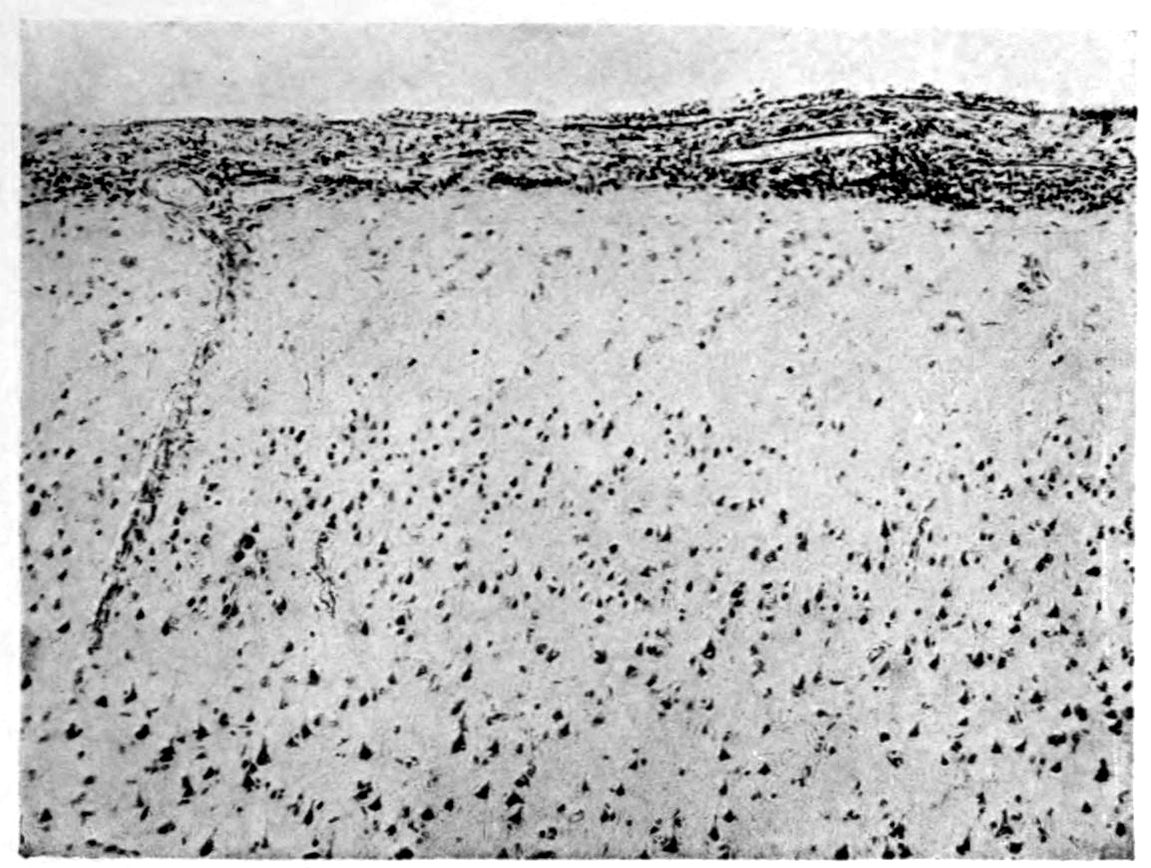

Apparent new formation of small blood vessel. Photographed by Dr. A. M. Barrett.

Rod cells (Stäbchenzellen) in paretic neurosyphilis. Photographed by Dr. A. M. Barrett.

Granular ependymitis—microscopic appearance of a marked example of “sanding” of ventricle.

41Characteristic and constant in paretic neurosyphilis is the Plasmocytosis and Lymphocytosis, Perivascular in distribution about small cortical vessels. There is also a characteristic (though characteristically less prominent) Plasmocytosis and Lymphocytosis, Meningeal in distribution. The pleocytosis of the spinal fluid, almost constant though variable in amount in life, is an indicator of the meningeal picture and less directly of the parenchymatous picture.

Granular Ependymitis (“sanding” of ventricle floors) is characteristic and may be regarded as part of the parenchymatous picture. This ependymitis is an indicator how chemical changes could be readily produced at least in the ventricular fluids, since the limiting membranes of the nerve tissue are here subject to multiple breaks. The “sanding” is a neuroglia reaction to these multiple small breaks (Weigert’s explanation).